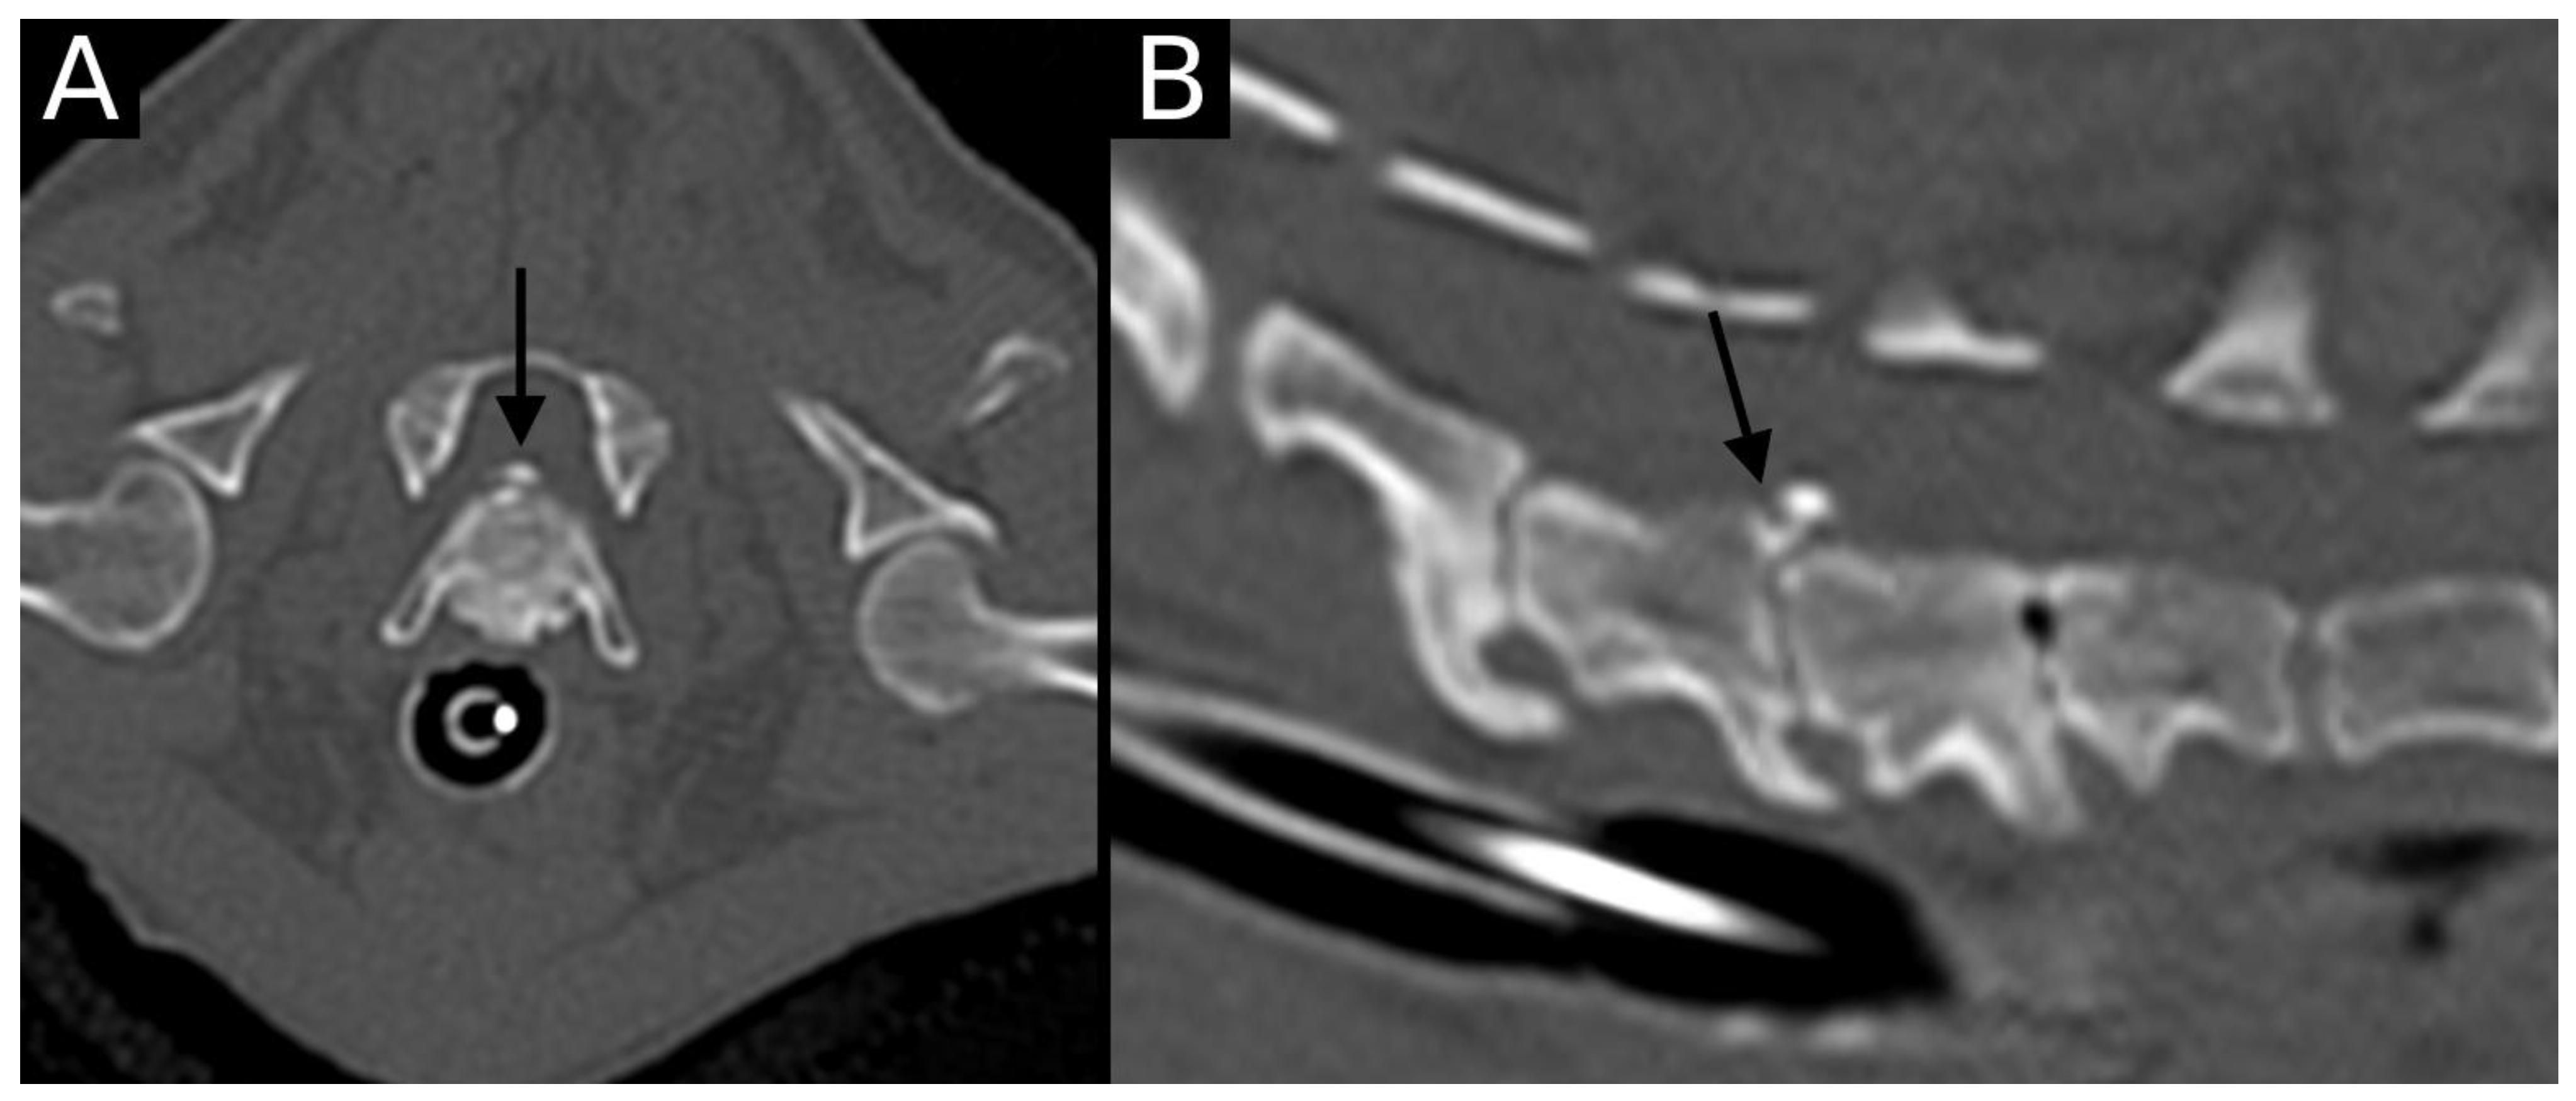

The junction between the endplates and intervertebral discs of the cervicothoracic junction (C6–C7, C7–T1 and T1–T2) were evaluated for the presence of alterations. When present, they were also graded and scored for EPJA, IVD herniation, spondylosis deformans, endplate sclerosis, articular process joint osteoarthrosis, and the presence of vertebral morphological abnormalities. The scoring system for endplate junction alterations and other spinal abnormalities was based on the proposed scoring by Tellegen et al. [13] for presumed EPJF at the lumbosacral spine. Endplate junction alterations were classified into four types (A, B, C, D): Type A involved presence of irregularity of the endplate margins without an obvious free fragment (Figure 1 and Figure 2); Type B involved avulsion evidenced by a thin rim of bone associated with a defect in the dorsal edge of the adjacent endplate (Figure 3); Type C included frank avulsion of a bony fragment (Figure 4) and Type D included presence of bony avulsion of both endplates. If EPJA was present, location (dorsal or ventral) and lateralization of the defect were also recorded. IVD herniation was graded from grades 0 to 3: grade 0 indicated no to mild (0–24%) herniation; grade 1 indicated mild to moderate (25–49%) herniation; grade 2 indicated moderate to marked (50–74%) herniation; grade 3 indicated marked herniation to complete obliteration (75–100%) of the vertebral canal by disc material. Spondylosis deformans was scored from grades 0 to 3: grade 0 indicated no enthesophytes; grade 1 indicated a small enthesophyte at the edge of the epiphysis that does not extend past the endplate; grade 2 indicated the presence of an enthesophyte that extends beyond the endplate but does not connect to the adjacent vertebra; and grade 3 indicated connecting enthesophytes from adjacent vertebrae forming a mineralized bridge. The other mentioned abnormalities (IVD mineralization, endplate sclerosis and articular process joint osteoarthrosis) were scored as present (1) or absent (0).

Figure 3. Transverse (A) and sagittal (B) reconstructions in bone algorithm. Contour irregularities lined by mild sclerosis are observed at the dorsal aspect of the T1 cranial endplate. A small, non-displaced mineral structure is observed at the same level (arrow). This is consistent with EPJA Type B.